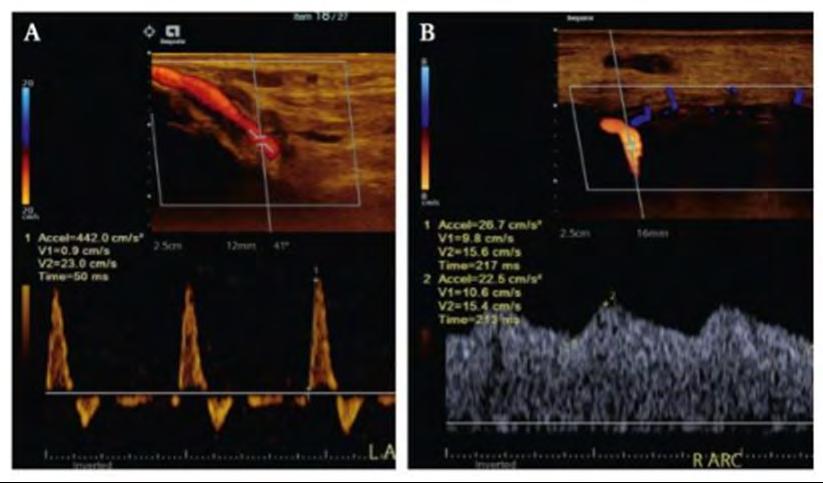

Traditional noninvasive tests for PAD include ABI (ankle brachial index) and TBI (toe brachial index). Both have limitations and can be unreliable in patients with noncompressible vessels (calcified vessels), wounds or amputations. This study aimed to assess how accurate pedal acceleration times are at diagnosing peripheral arterial disease (PAD) in patients already suspected of having the disease. PAT measures the time it takes blood to accelerate in the foot’s arteries using Doppler ultrasound and is usually measured in 4–5 arteries within the foot (Fig. 1). PAT values increase proportionally to the severity of PAD and return a zero value in occluded or dormant vessels where no flow is seen or recorded.

Figure 1: Pedal acceleration times in a (A) normal (50 ms) and (B) abnormal (213 ms) artery.